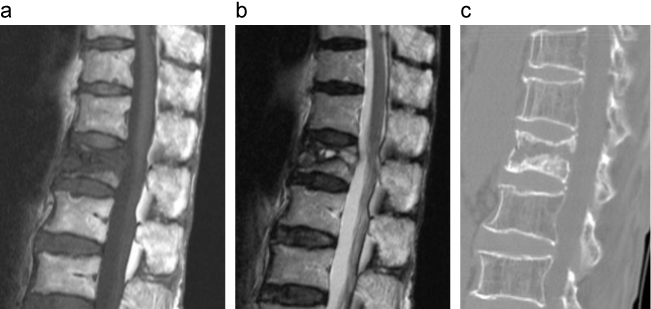

椎体骨折後骨癒合不全のMRI、CT画像

診察時には、手術適応となる因子がないか検討する必要がある。

a:MRI T2強調画像

b:CT画像

出典

img

1: 著者提供